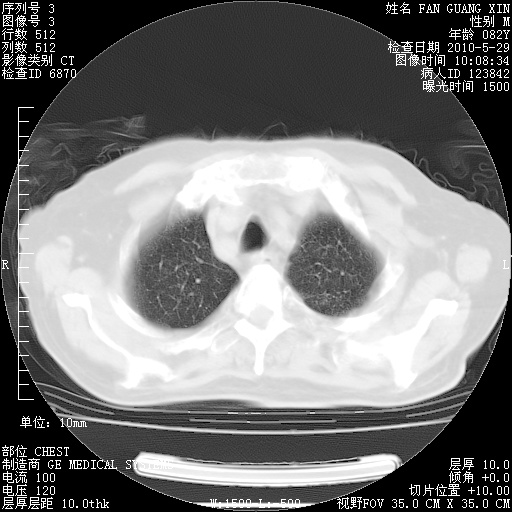

还需要哪些辅助检查?我们医院排除真菌感染没有任何检验方法,胸片好像能够排除肺部真菌感染。